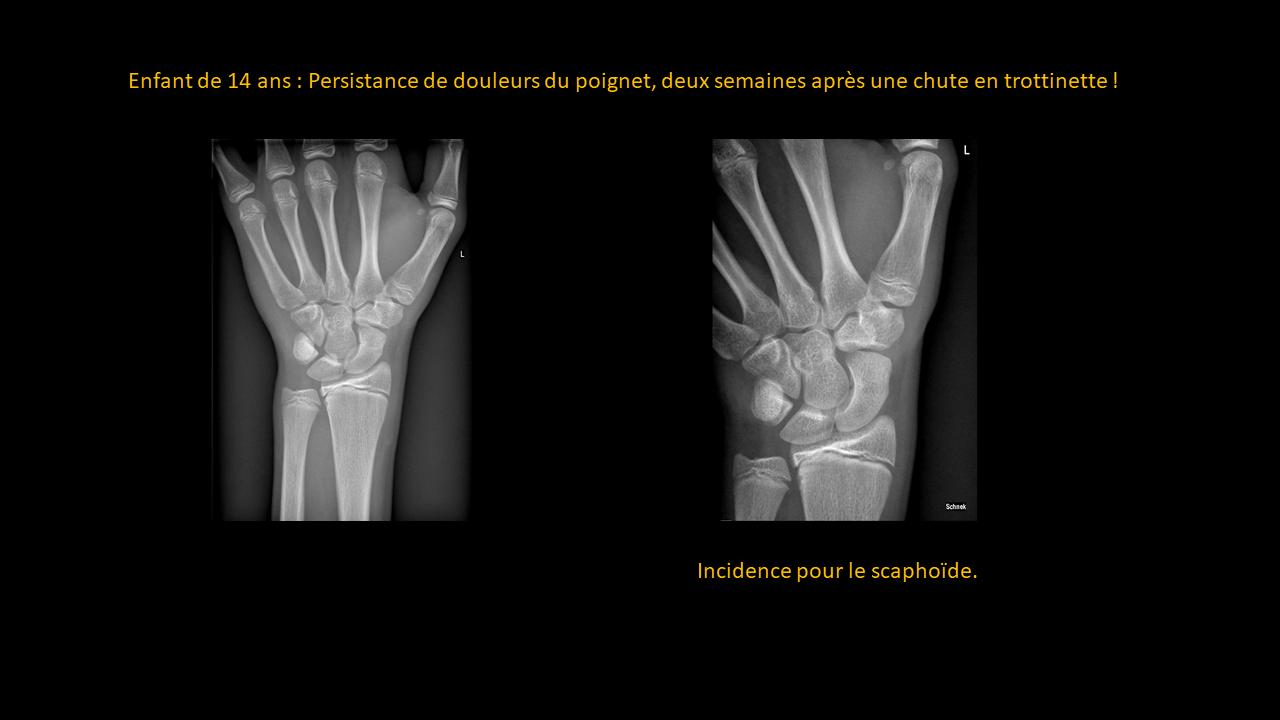

Présentation clinico-radiologique 85

_______ cliquer ici pour la réponse ________